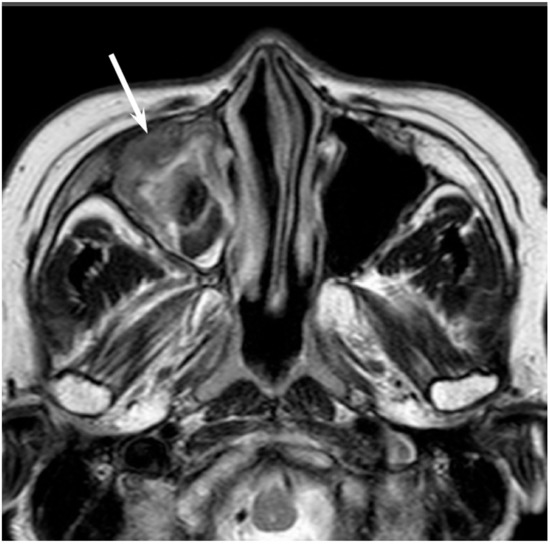

On CT, ONBs appear as a homogeneous, well-defined soft-tissue mass. Scattered speckled calcifications may be observed within the tumor. The tumor commonly extends into the ethmoid and maxillary sinuses, but rarely involves the sphenoid sinus. CT is essential for the evaluation of osseous involvement of the cribriform plate, fovea ethmoidalis, and lamina papyracea. On MRI, ONBs usually show hypointensity relative to the gray matter on T1WI and hyperintensity relative to the gray matter on T2WI [33]. These tumors demonstrate an avid and homogeneous enhancement except for occasional areas of necrosis or hemorrhage (Figure 7). When an intracranial extension is present, the peripheral or marginal cysts are a characteristic and specific feature of ONBs [34].

Figure 7. Olfactory neuroblastoma of the right nasal cavity. Contrast-enhanced CT image showing a homogeneously enhanced lesion in the right olfactory cleft (arrow).